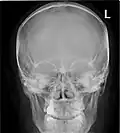

![]() Paranasal sinuses seen in a frontal view | |

Paranasal sinuses radiograph (occipitofrontal)